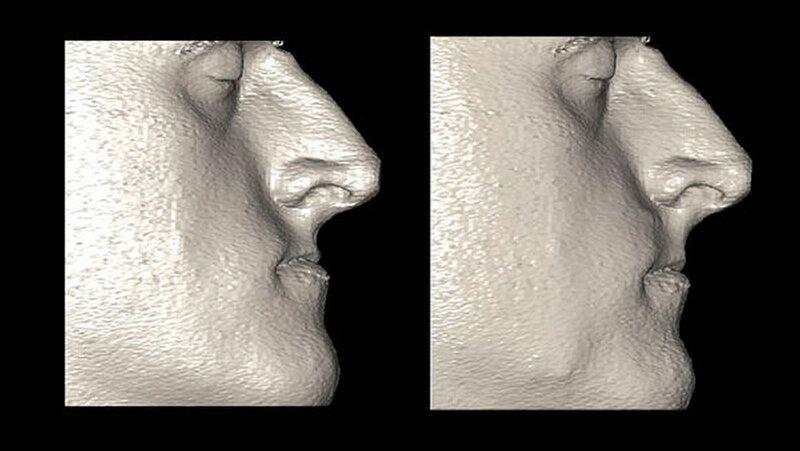

Die Abbildungen 1 und 2 zeigen die klinische Situation bei Erstvorstellung: Der Unterkiefer ist zu prominent. Der Oberkiefer und das Mittelgesicht liegen zurück. In der Front liegt ein umgekehrter Überbiss vor. Der Unterkiefer steht vor dem Oberkiefer. Das erschwert das Abbeißen und Kauen der Nahrung. Die Scans (siehe Abbildungen) dokumentieren, wie aufwendig die virtuelle Operationsplanung erfolgen musste.

Gesichtsscanner: Hochtechnologie für mehr Patientensicherheit

Künftig kann das postoperative Ergebnis mittels eines Gesichtsscanners der neuesten Generation noch besser für den Patienten vorhersagbar werden. Hochtechnologie für genauere Vorhersagbarkeit des OP-Ergebnisses und damit gesteigerte Patientensicherheit. Da es sich hierbei um ein ganz neues Verfahren handelt, stehen Langzeituntersuchungen und -auswertungen noch aus.